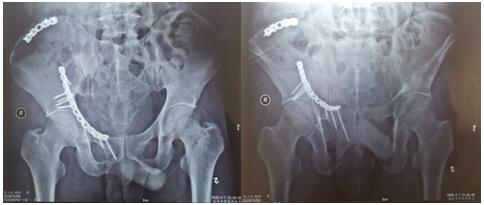

術(shù)后影像學(xué)資料如下:

骨盆骨折多由高能量損傷所致,多伴有合并癥或多發(fā)傷,處理棘手,致殘率高達50%~60%。經(jīng)過孟澤祖主治醫(yī)師、李鵬鵬住院醫(yī)師的精心管理與辛勤付出,患者曹某腰椎骨折術(shù)后病情恢復(fù)良好。于2020年4月1日在全麻下行骨盆粉碎性骨折切開復(fù)位內(nèi)固定術(shù),患者多處骨盆粉碎性骨折,病情復(fù)雜,手術(shù)時間長,術(shù)中出血多。首次采用改良stoppa+右髂后上棘聯(lián)合入路,手術(shù)順利,術(shù)后病情不穩(wěn)定,經(jīng)過主管醫(yī)師孟澤祖與全科骨干醫(yī)師、護士的通力合作與堅守,術(shù)后病情日趨穩(wěn)定。復(fù)查下肢血管超聲提示:未見明顯血栓。患者曹某在我院經(jīng)過標(biāo)準(zhǔn)化、專業(yè)化的綜合治療后,患者病情恢復(fù)良好,神經(jīng)損傷癥狀已基本恢復(fù),傷口I級愈合,患者帶著滿意的笑容康復(fù)出院了。